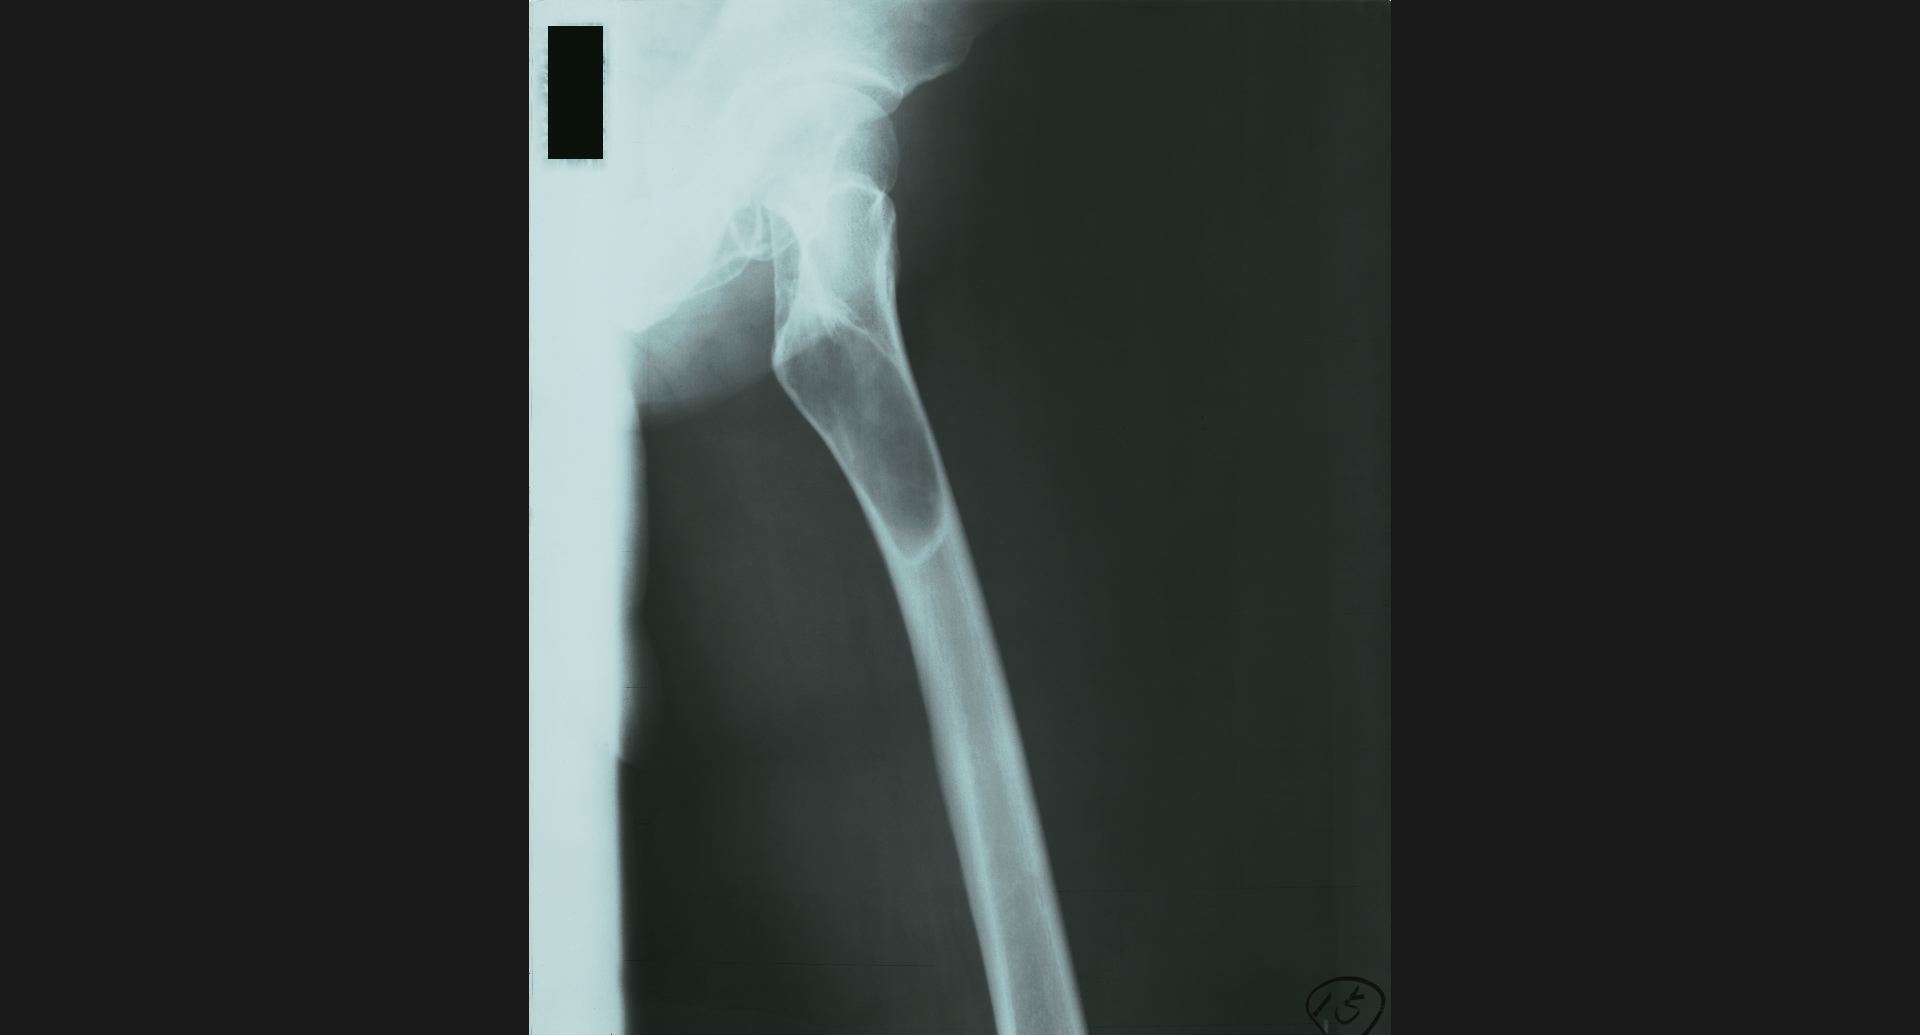

fig.15(55KB) :Fibrous dysplasia

骨頭のtrabeculation。病変部。